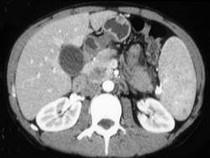

问题 女,56岁,腹部胀痛不适、食欲减退,影像表现如下图,最佳诊断是 ( )

选项 A.急性胰腺炎 B.慢性胰腺炎 C.胰腺腺癌 D.胰腺转移癌 E.胰腺假性囊肿

答案 C